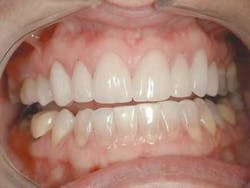

For the most visually pleasing effect, the teeth should have a slight mesial axial inclination. The observation of our patient's teeth reveals inclinations that do not follow this rule (Fig. 4 – black lines are desired; yellow lines existing).

The final result of this case sees an improvement in all of the original objectives (Figs. 12, 13, 14). Our patient wanted a lighter, wider smile that would cover the darkness she had lived with her entire life. Needless to say, she was ecstatic with the end results (Figs. 15, 16).